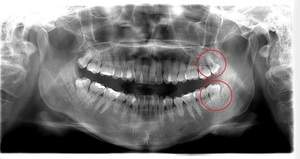

左下親知らずがたまに痛み、

できれば痛くなく抜きたい症例

- 抜歯前写真(レントゲン)

- 抜歯前写真(CT画像)

| 年齢 | 20代・女性 |

|---|---|

| 主訴 | 左下親知らずがたまに痛み、できれば痛くなく抜きたい |

| 親知らずの生え方 | 完全に埋まっている、横向きに生えている |

| 抜歯時間 | 50分 |

| 費用 | 約8,000円(保険診療、CT代含む) |

| 抜歯内容 | 左下親知らずが横向きになって半分埋まっている状態だったため、麻酔を行い、親知らずの奥の歯ぐきに切開をいれ、歯が囲んでいる骨を削り、歯の頭の部分を削って出し、その後根の部分に器具をかけて抜歯しました。 親知らずが一部神経に近い部分があったため、術後に麻痺が出る可能性がありました。このケースでは事前にCTを撮影し、歯の位置、根の方向、神経との距離を確認していたため、幸い麻痺が出ることはありませんでした。 術後1週間経過して糸取りをして治療は終了となりました。抜歯後3日間は腫れと痛みで大変だったが、糸取りをする頃には痛みも腫れも無くなったと患者さまも喜んでおられました。 |